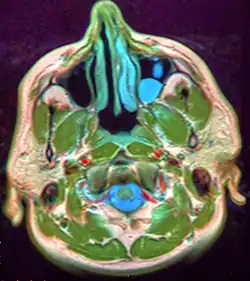

Oral mucocele (also mucous extravasation cyst, mucous cyst of the oral mucosa,[1] and mucous retention and extravasation phenomena) is a condition caused by two related phenomena - mucus extravasation phenomenon and mucous retention cyst.

Mucous extravasation phenomenon is a swelling of connective tissue consisting of a collection of fluid called mucus. This occurs because of a ruptured salivary gland duct usually caused by local trauma (damage) in the case of mucous extravasation phenomenon and an obstructed or ruptured salivary duct in the case of a mucus retention cyst. The mucocele has a bluish, translucent color, and is more commonly found in children and young adults.

The size of oral mucoceles vary from 1 mm to several centimeters and they usually are slightly transparent with a blue tinge. On palpation, mucoceles may appear fluctuant, but can also be firm. Their duration lasts from days to years,[4] and may have recurrent swelling with occasional rupturing of its contents.